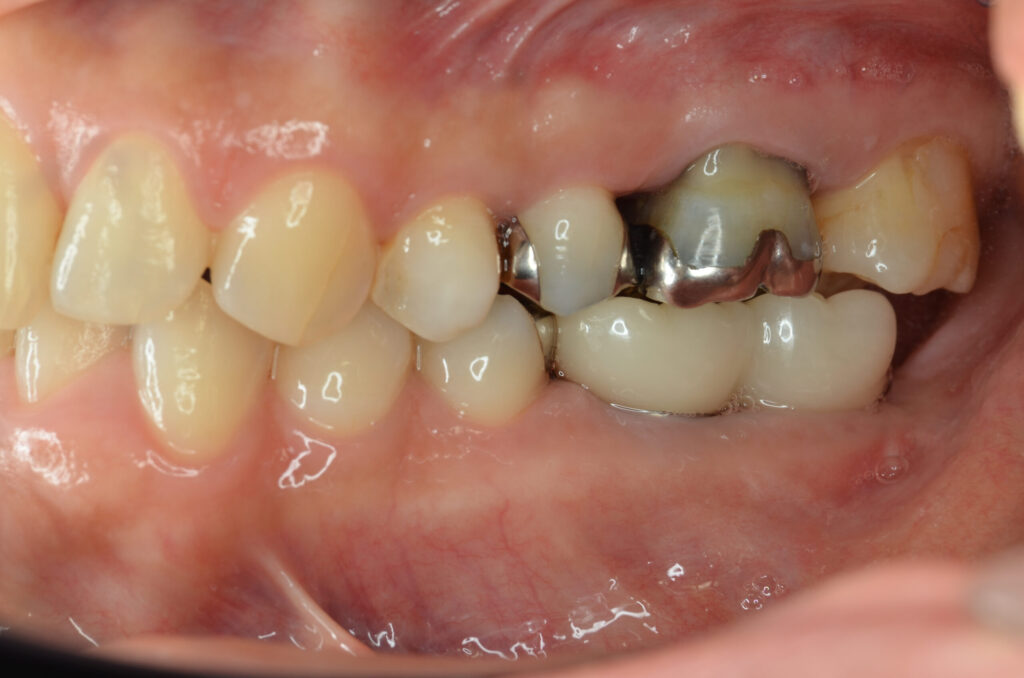

Before

After

治療内容

インプラント2本・骨造成併用

治療期間・回数

約4ヶ月・約4回

費用

880,000円

治療のリスク

外科手術が必要になるため、患者様に体力的な負担がかかる。